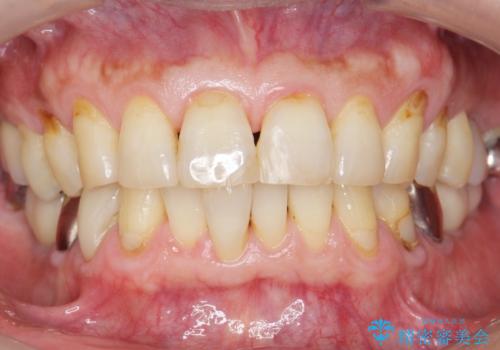

奥歯のインプラント ソケットリフト 60代男性

- 奥歯のインプラントをご希望し、来院された患者様です。

審美的・機能的な仕上がりに喜んで下さいました。

また、半年という比較的短期間でインプラント治療が終わったことにもご満足頂けました。